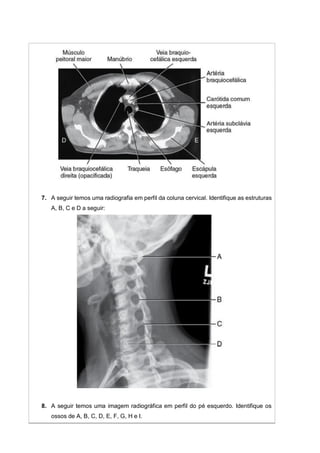

7. A seguir temos uma radiografia em perfil da coluna cervical. Identifique as estruturas

A, B, C e D a seguir: